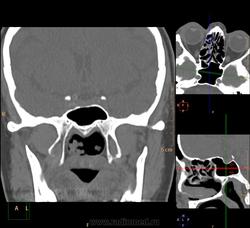

Спонгиоз одной из половин пазухи, пациент 35 лет: